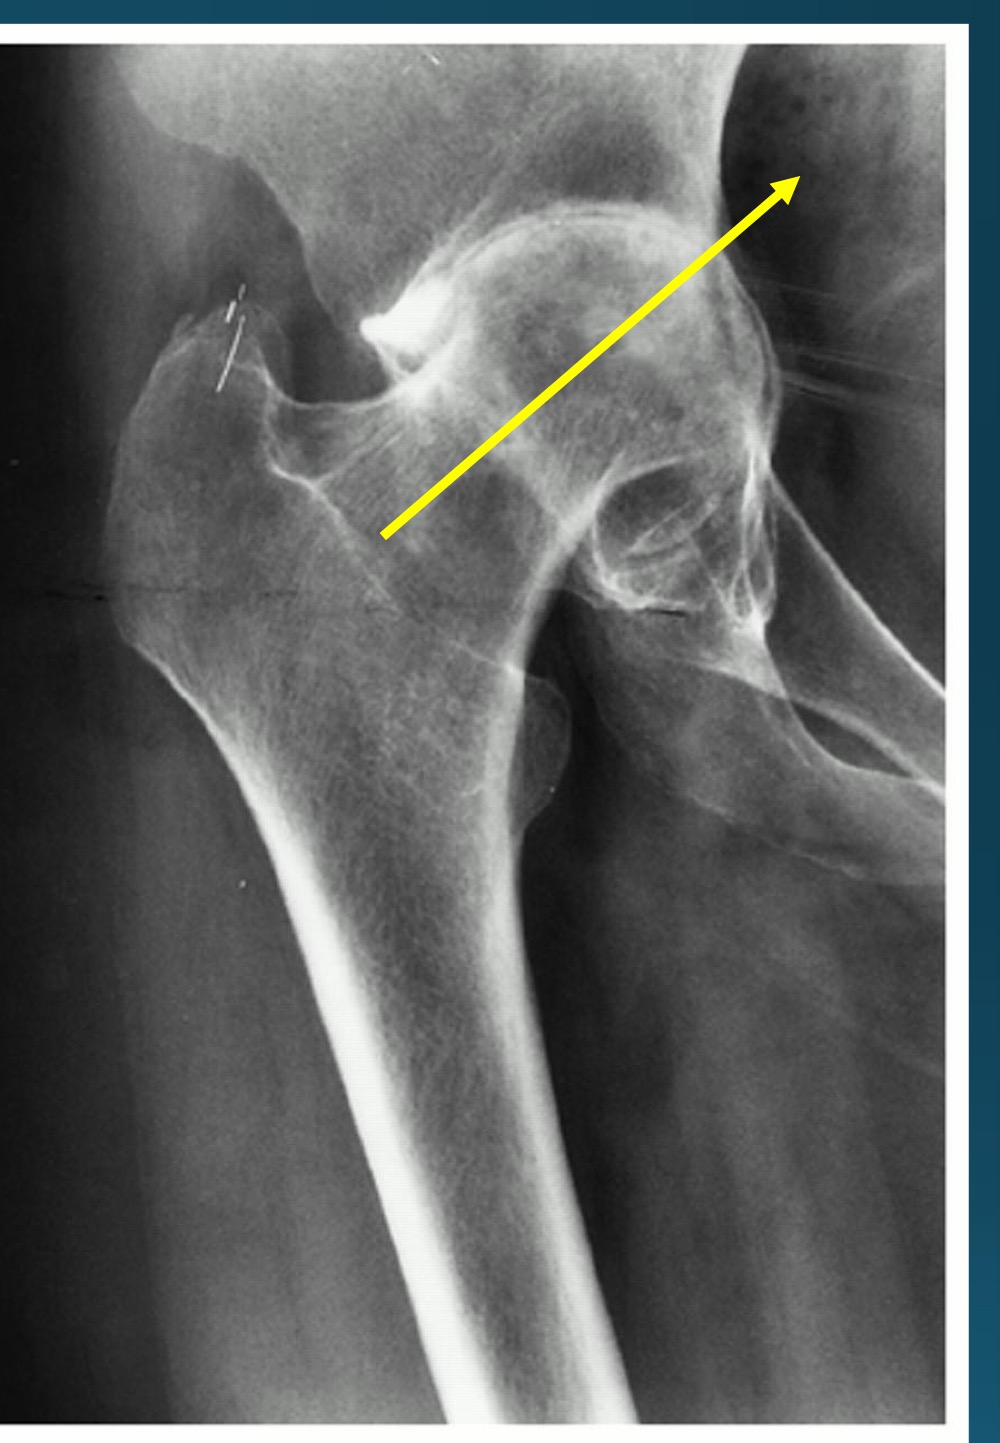

what finding is in this image

hypertrophic neuropathic arthropathy

what is the finding in this image? AKA

neuropathic arthropathy AKA charcot’s joint